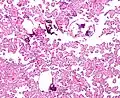

Micrograph of a choroid plexus papilloma. H&E stain.

Histopathology

The tumor is neuroectodermal in origin and similar in structure to a normal choroid plexus. They may be created by epithelial cells of the choroid plexus. Papillary fronds lined by bland columnar epithelium are visible under the microscope. Normal absences include mitotic activity, nuclear pleomorphism, and necrosis.[10] Tumors have positive immunohistochemistry for cytokeratin, vimentin, podoplanin, and S-100.[11] Up to 20% of choroid plexus papilloma patients may test positive for glial fibrillary acidic protein (GFAP).[12] Studies have found that fourth ventricle cancers express more S100 than lateral ventricle tumors, and older patients (over 20 years) express more GFAP and transthyretin than younger patients.[13] Some individuals with choroid plexus papilloma have germline TP53 gene mutations, according to genetic analyses.[14] These cancers rarely exhibit nuclear p53 protein positivity. Aicardi syndrome, hypomelanosis of Ito, and 9p duplication are syndromic correlations of choroid plexus papilloma.